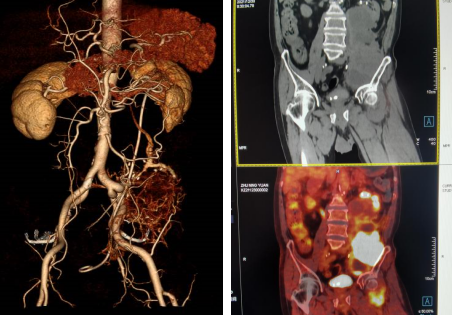

术前腹腔血管CTA(图左)、PET-CT(图右)

袁大爷一家人在绝望前,通过熟人介绍来到betway在线登陆。普外科韩锡琳主任接诊时发现袁大爷的肿瘤体积为29*10*7cm,并且已经包裹输尿管及部分肾脏,侵犯左侧股神经,压迫大血管。通过与袁大爷的沟通,了解其目前被病痛折磨的无法正常生活,放、化疗对其无效,手术是唯一希望,韩主任立即安排袁大爷住院接受治疗。

位于腹膜后肿瘤是传统外科的“手术禁区”,腹膜后解剖结构复杂,腹膜后血管、神经丰富,包含肾脏、输尿管等,紧邻脊柱、腰大肌等重要脏器及血管,手术风险高,损伤的后果非常严重。